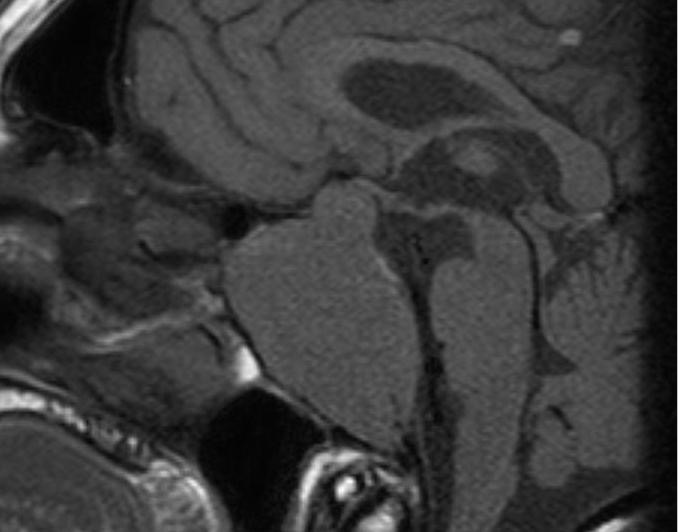

Figure 12. A sagittal T1 weighted unenhanced image shows an invasive macroadenoma which has involved much of the central skull base. It has invaded the sphenoid air sinus which can no longer be identified and has also extended down the clivus. There is also a modest suprasellar extension with elevation of the optic chiasm.